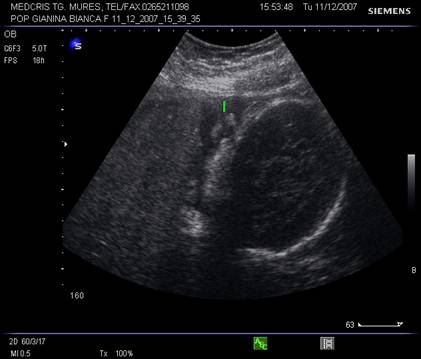

Rinichii - sectiunile transversale la nivel lombar fetal identifica retroperitoneal, cel mai devreme la 13 saptamani, de obicei la 17 saptamani, doua zone inomogene, moderat ecogene. [1,13]

O usoara dilatatie a pielonului la 5 mm este vizibila in trim. II. Cresterea dilatatiei va ridica suspiciunea de trisomie 21. [8]

Sectiunile paravertebrale longitudinale vor defini structuri renale ovale cu parenchim hipoecogen si ecogenitate crescuta in pielon.

Raportul dintre circumferinta renala si cea abdominala ramane constanta pe parcursul sarcinii, la 0,27 - 0,30.[8]